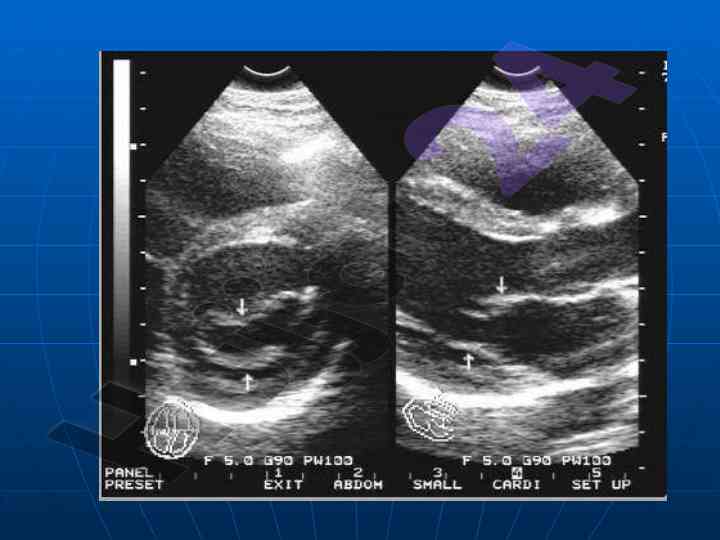

Ushbu maqolada yurak va qon-tomir kasalliklarining nurlanish tashxisi bo'yicha ma'lumotlar keltiriladi. U echokardiofragiya va angiografiya usullarini o'z ichiga oladi. Maqola universitetning tibbiy fakultet talabalariga yo'naltirilgan.